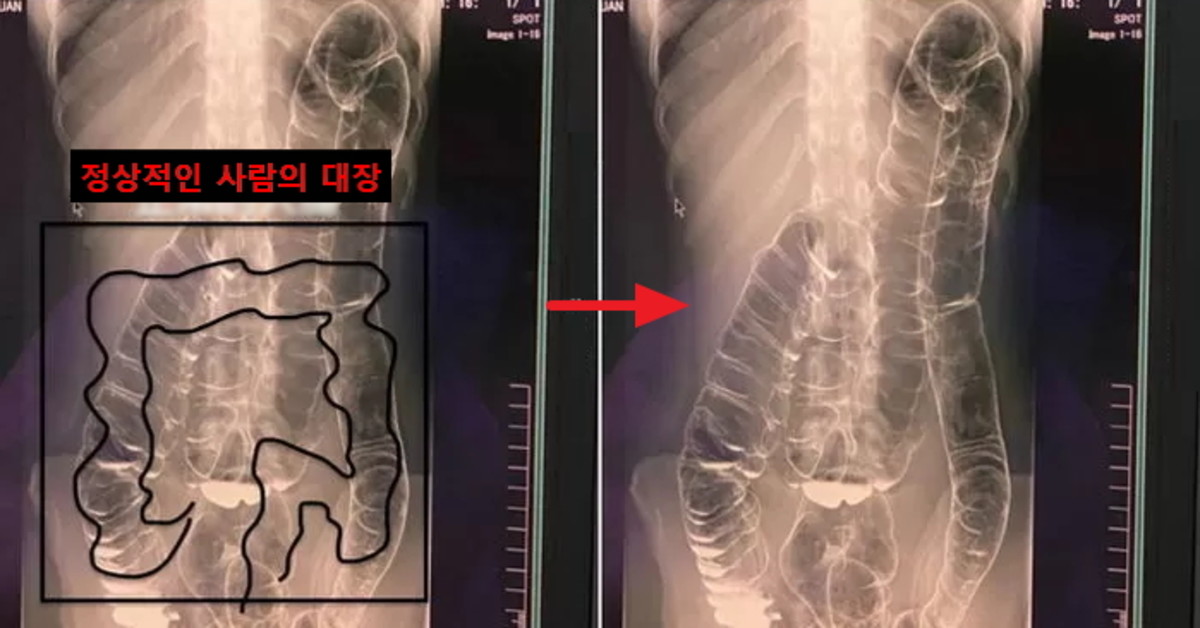

(왼) 정상적인 사람의 대장, (오) A씨의 대장 / Dcard

A씨의 대장은 그동안 처리하지 못한 대변이 축적되어 심장 부분까지 치솟아 있었다. 심지어 대장의 주름이 팽팽하게 펴진 부분도 확인할 수 있었다.